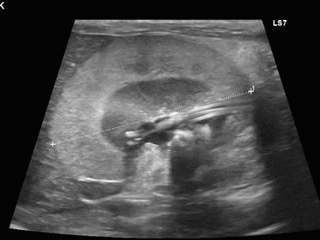

他院より紹介されたケース、この猫ちゃんは左右尿管に 結石(矢印)が詰まっていました。

尿管結石が原因で腎臓は水腎症になっていました。

左右の尿管結石が同時に詰まってしまい左の尿管が破裂(矢印)していました。

尿管結石2箇所以上閉塞による水腎症。

内科的な治療にも反応せず、SUBシステムをいれることになりました。